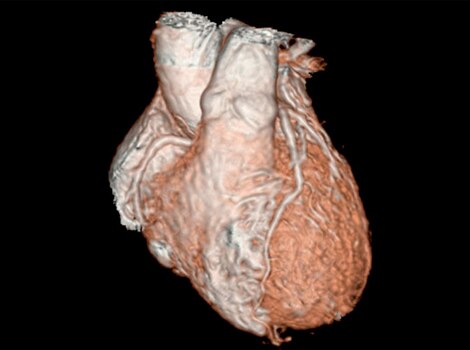

Revolution CT & CardioGraphe4

Achieve one-beat, whole heart acquisition for imaging or comprehensive cardiac assessment with or without beta blockers at any heart rate.5

Revolution CT & CardioGraphe7

Achieve one-beat, whole heart acquisition for imaging or comprehensive cardiac assessment with or without beta blockers at any heart rate.8

Revolution CT & CardioGraphe3

Achieve one-beat, whole heart acquisition for imaging or comprehensive cardiac assessment with or without beta blockers at any heart rate.4 Read More

Achieve one-beat, whole heart acquisition for imaging or comprehensive cardiac assessment with or without beta blockers at any heart rate.4